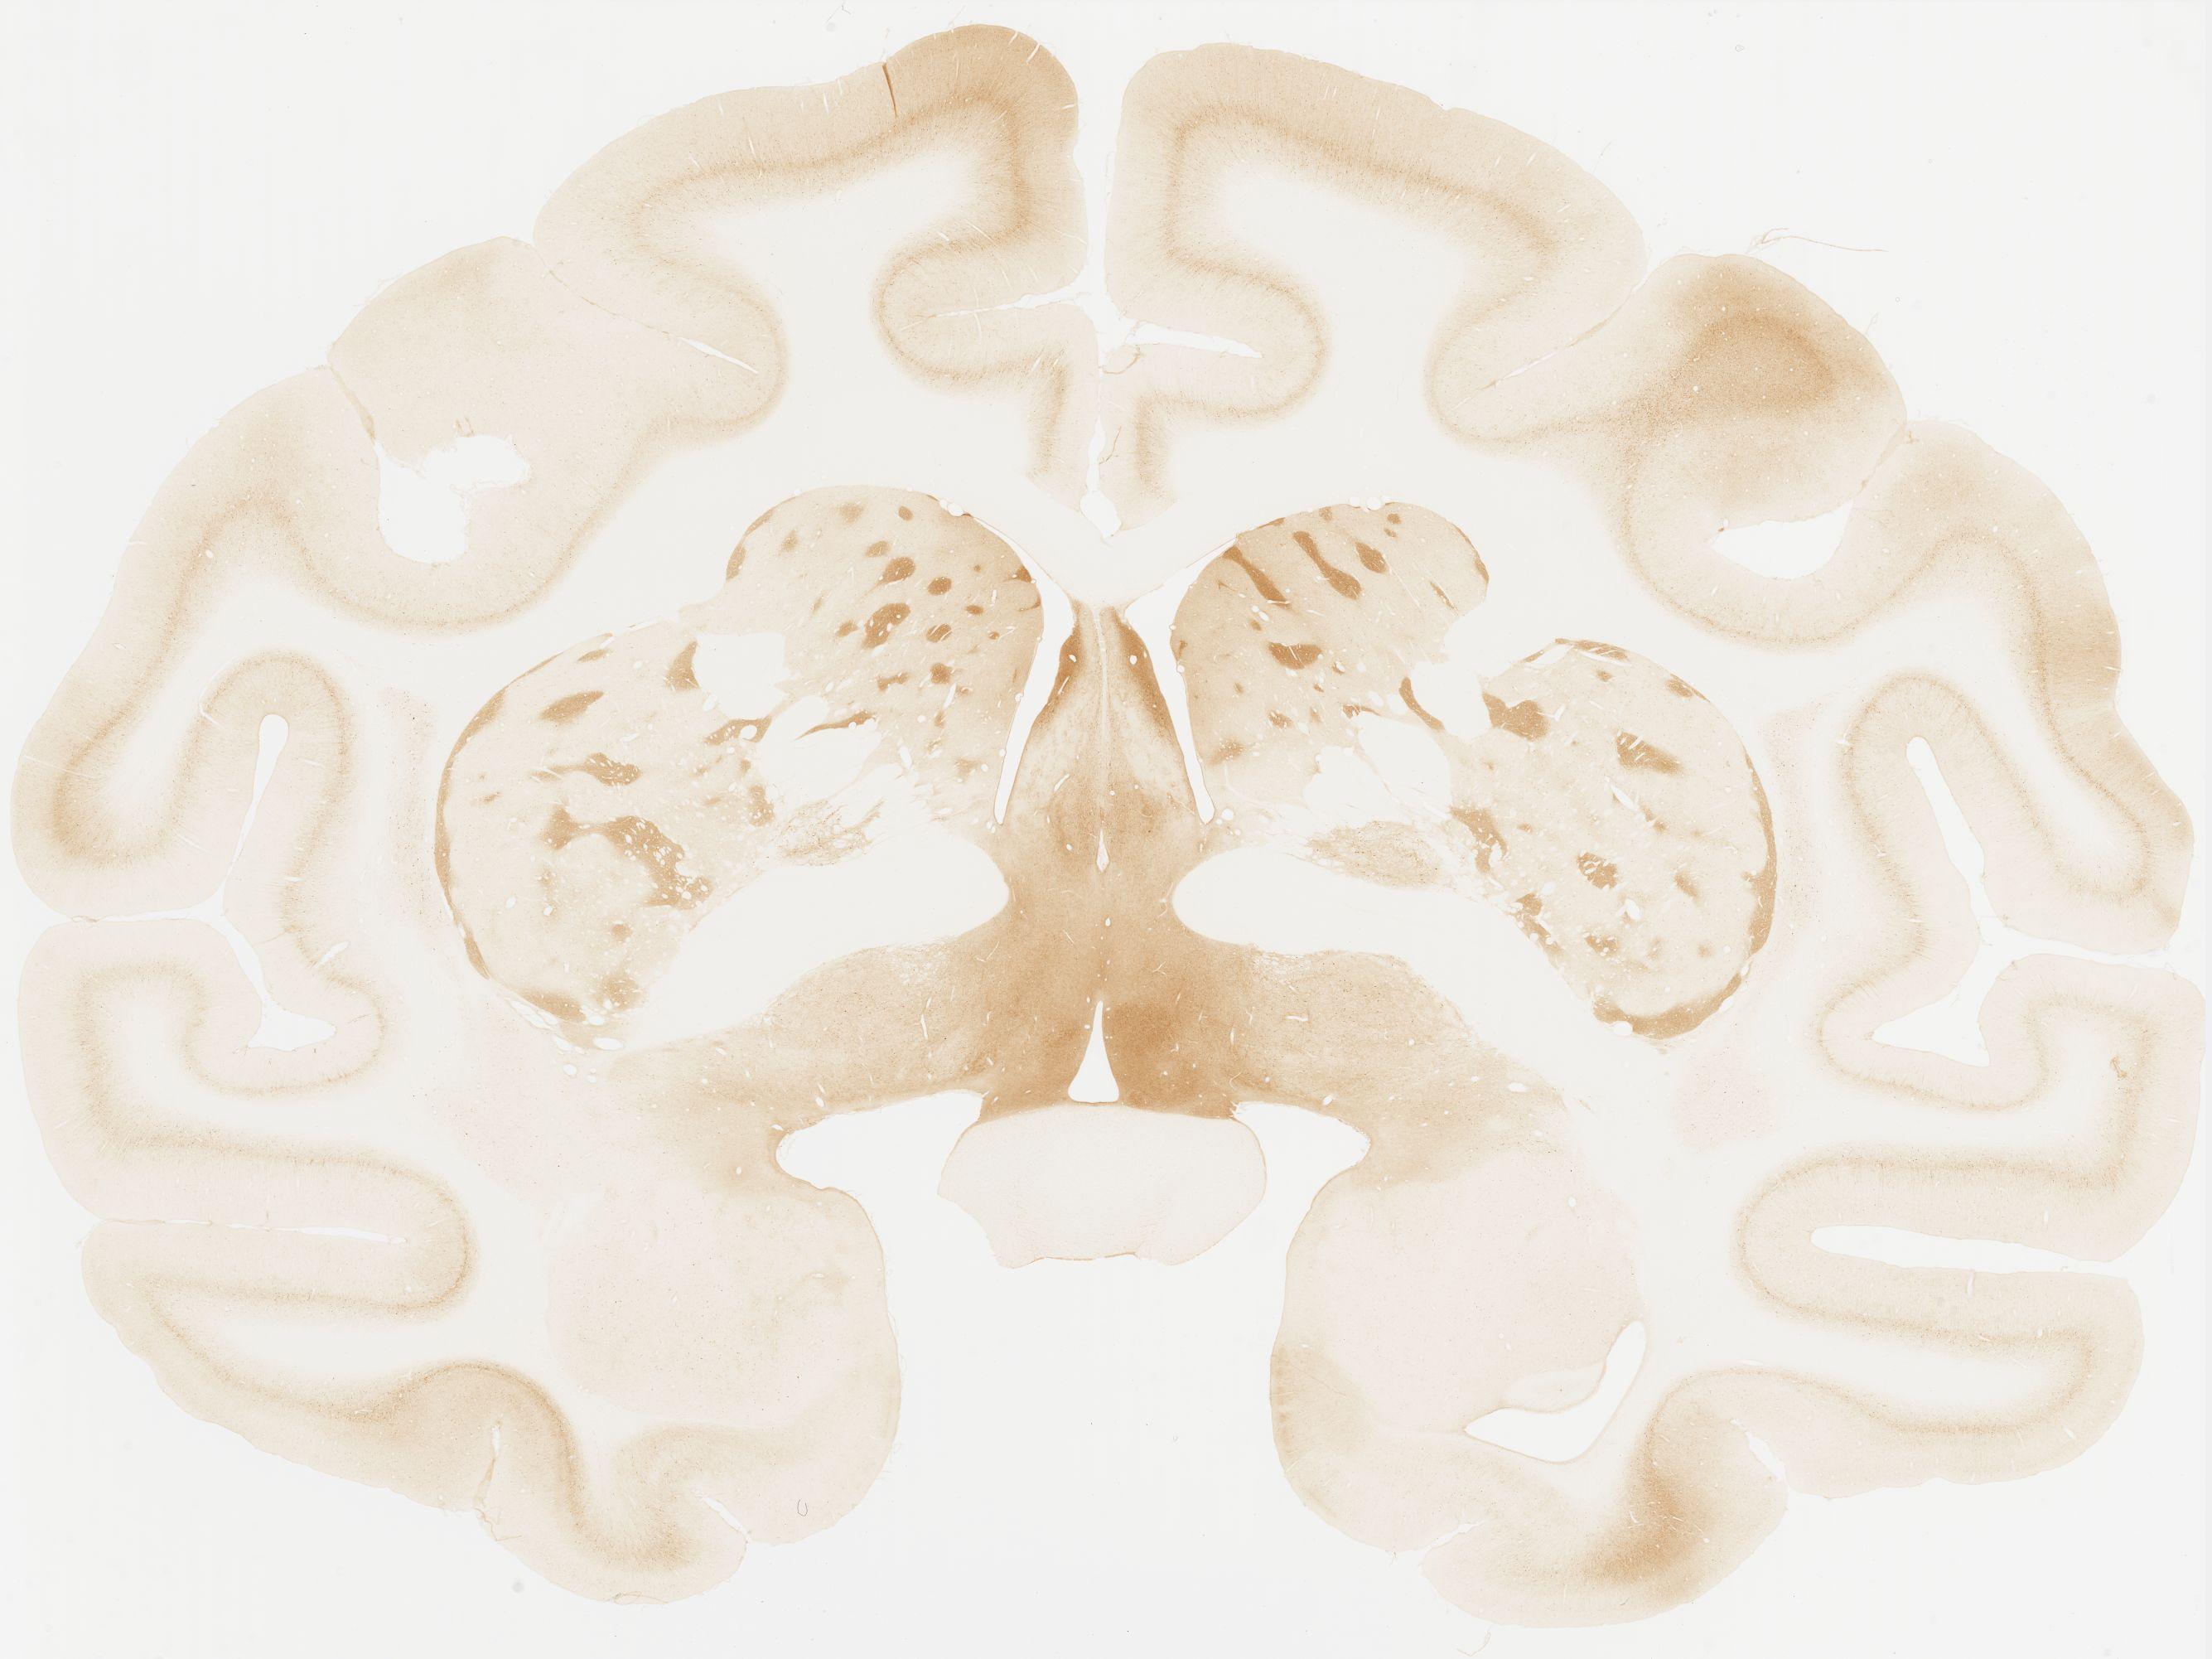

Datasets -> Macaca Fascicularis -> KChIP1, (Potassium Voltage-Gated Channel-Interacting Protein 1), coronal, immuno, Whole-Brain, adult

[ Metadata ]   ·   Source: Edward G. Jones